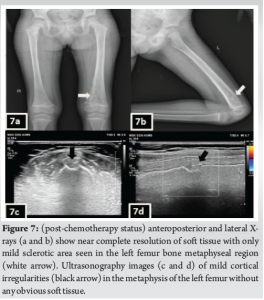

A 3-year-old female was brought to the pediatric orthopedic department with complaints of swelling over her left leg for 2 months. The swelling was insidious in onset, progressive in nature, associated with pain which was aggravated by movement, more at night, and associated with fever and local rise of temperature. According to the mother, weight loss and loss of appetite were noted. No history of abdominal pain. An X-ray of the left thigh was requested. It revealed an ill-defined subtle expansile lytic lesion in the diaphysis and distal metaphysis region of the left femur with the suggestion of lamellated (onion peel) and sunburst (in a few areas) types of periosteal reaction (Fig. 1). No evidence of fracture was noted. Laboratory results were as follows; white blood cell – 7220 cells/μL, hemoglobin – 6.8 g/dL (decreased), hematocrit – 24%, platelets – 190,000/μL, C-reactive protein (CRP) – 81.5 mg/L (raised) and lactate dehydrogenase (LDH) – 467.99 U/L (raised). The differential diagnosis of primary bone tumor (Ewing’s sarcoma > osteosarcoma) and osteomyelitis was considered initially. (High Resolution Sonography)left thigh was done, which revealed soft tissue showing significant vascularity on color Doppler with associated spiculated sunburst type of periosteal reaction (Fig. 2). A provisional diagnosis of primary bone tumor was made and as a part of metastatic screening, ultrasonography of the abdomen was advised. It revealed a large ill-defined heterogeneous retroperitoneal mass crossing the midline, encasing the aorta and its branches. The mass was seen insinuating beneath the aorta, lifting it off the vertebral column. Multiple enlarged pre/para-aortic lymph nodes and bilateral common, external, and internal iliac vessels were noted (Fig. 3). To further characterize the abdominal mass, the contrast-enhanced computed tomography (CECT) chest with the abdomen covering the thigh was done. It revealed a large heterogeneous solid mass lesion epicenter in the left suprarenal region measuring 10 × 6.6 × 11.6 cm in maximum orthogonal dimensions and crossing the midline. It shows multiple amorphous and chunky calcifications within. The mass is heterogeneously enhanced with areas of necrosis and is encasing and displacing the abdominal aorta. The left adrenal gland was not seen separately and mass is seen displacing the left kidney inferiorly and laterally. Multiple enlarged heterogeneously enhancing retroperitoneal lymph nodes are seen along with bony metastatic lesions (Fig. 4). Based on these findings, the primary diagnosis of left suprarenal neuroblastoma with multiple lymph-nodal and bony metastasis was made. Ultrasound (USG)-guided tru-cut biopsy of the left suprarenal mass was performed, which revealed small round blue cell tumor cells arranged in sheets and nests. Bone marrow trephine biopsy taken from bilateral posterior superior iliac spine revealed metastatic deposits of small round blue cell tumor. These cells were positive for synaptophysin, chromogranin, and cluster of differentiation-99 and negative for leukocyte common antigen confirming the diagnosis of neuroblastoma (Fig. 6). Eight cycles of neo-adjuvant chemotherapy were given to the patient. A metaiodobenzylguanidine scan post-chemotherapy revealed no residual bony metastasis. Positron emission tomography-computed tomography (PET-CT) was also done which revealed a non-fludeoxyglucose tissue mass noted in the left suprarenal region with an unremarkable musculoskeletal system. Follow-up CECT abdomen with the chest was done to assess chemotherapy response and for pre-operative planning which revealed a significant reduction in size and extent of the lesion with a significant reduction in number and size of retroperitoneal lymph nodes (Fig.5,7). Surgery was done and the residual lesion was removed. The patient is now on follow-up.